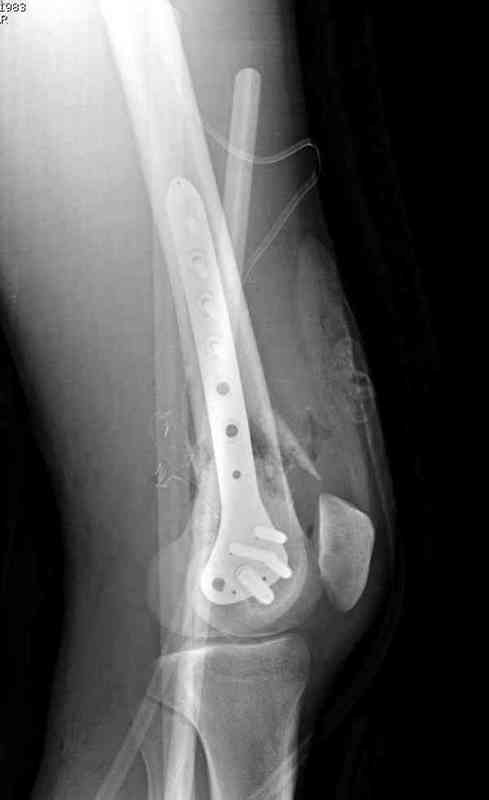

Предпочтительно фиксацию провести пластинами, во-первых, можно было сделать квадрицепс-пластику по Judet для восстановления движения в суставе, а потом коррекцию и фиксацию кондилярной пластиной с угловой стабильностью. Стерильный турникет на конечность поможет уменьшить кровепотерю во время операции.

До выхода Locking Plate, 95 градусная Blade Plate считалась одним из первых locking concept и фаворитов в лечении супракондилярных переломов и осложнений, потому что лезвие внедряясь параллельно к суставу, что создавало хорошую фиксацию. Для усиления фиксации иногда применяли Schuhli nut, чтобы блокировать шуруп в отверстии

(первый прототип locking concept)

Вчера утром поступил больной с огнестрельной раной, осмотрен сосудистым специалистом, сделана ангиограмма (снимки) Во время операции при вскрытии обнаружили кровотечение, рану забили салфетками, установили пластину locking DePuy.